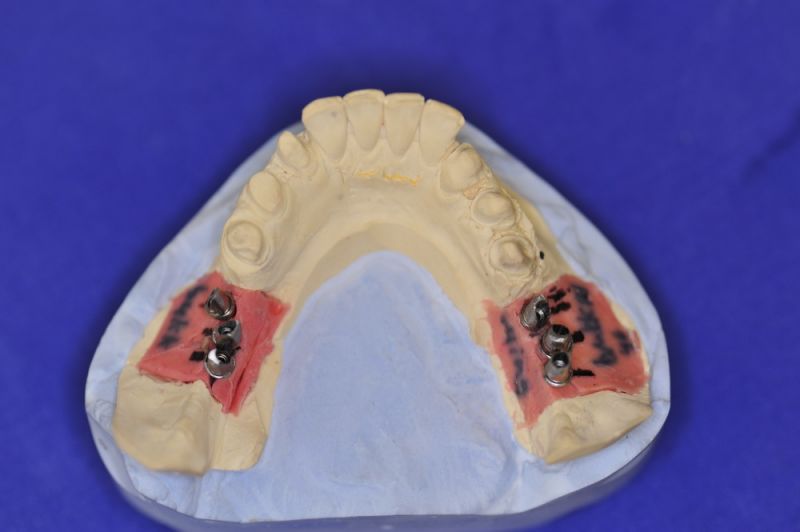

Es wurden sechs Implantate inseriert und diese wuchsen, trotz vielerlei Bedenken knöchern ein.

Nun stellte sich heraus, dass der Abstand zwischen den Implantaten sehr gering war, weil die Einschubrichtungen der Aufbauten sich zum Teil gegenseitig im Wege standen. Konfektionierte Teile mussten individuell umgeschliffen werden, dabei das Ziel, den Biss korrekt einzustellen nicht aus dem Auge zu verlieren.

Heute war nun Gerüsteinprobe, mit all den Problemen der Umsetzung zwischen Laborsituation und Mundsituation. Siehe Stichpunkt "Schnittstellenproblematik"! was bei Zähnen, auf Grund deren Eigenbeweglichkeit im Kieferkochen kein Problem wäre, ist bei drei unbeweglichen Implantaten ein Riesenproblem. Darüber spricht nur in aller Regel Niemand! Es musste viel fein nachgearbeitet werden.

Es sieht gut aus und das größte Problem besteht nunmehr darin die Arbeit so zu gestalten, dass die Patientin in der Lage ist diese Arbeit mit kleinen Interdentalraumbürsten zu säubern. Technisch ist diese Möglichkeit in der Arbeit angelegt und für die Patientin durchführbar.